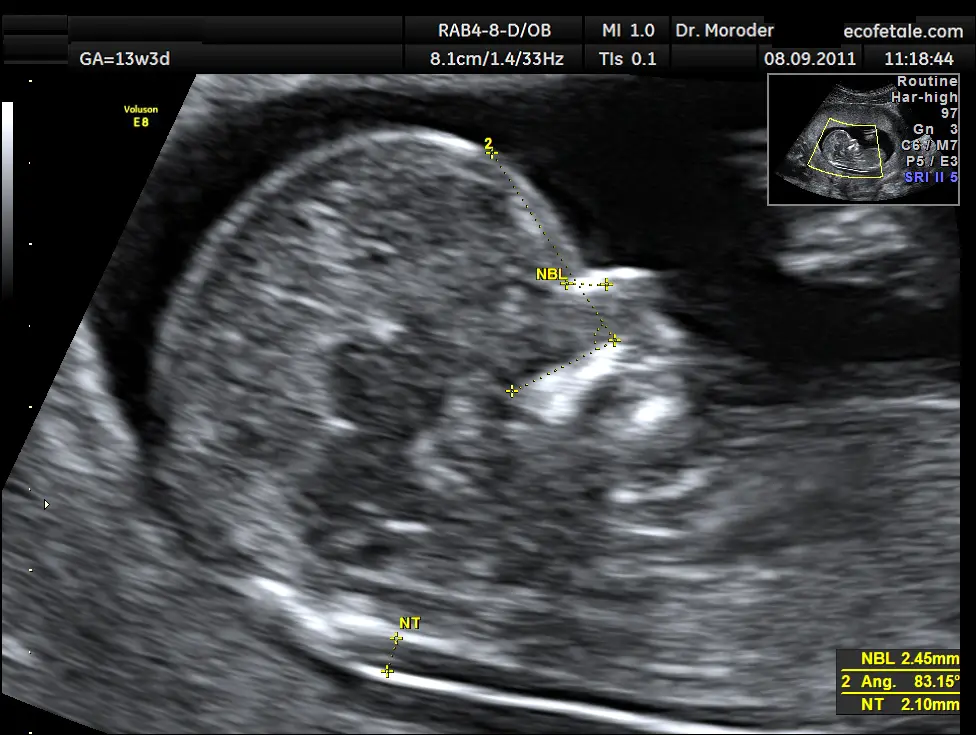

Die Nackenfalte wird während der Ultraschalluntersuchung im ersten Trimester gemessen. Der Arzt oder die Ärztin misst die Dicke der Nackenfalte mit Hilfe eines Ultraschallgeräts. Die Messung erfolgt in Millimetern.

Die Messung der Nackenfalte ist ein wichtiger Bestandteil der vorgeburtlichen Diagnostik. Sie kann helfen, das Risiko für chromosomale Anomalien abzuschätzen und die Eltern zu informieren, welche weiteren Untersuchungen notwendig sein könnten.